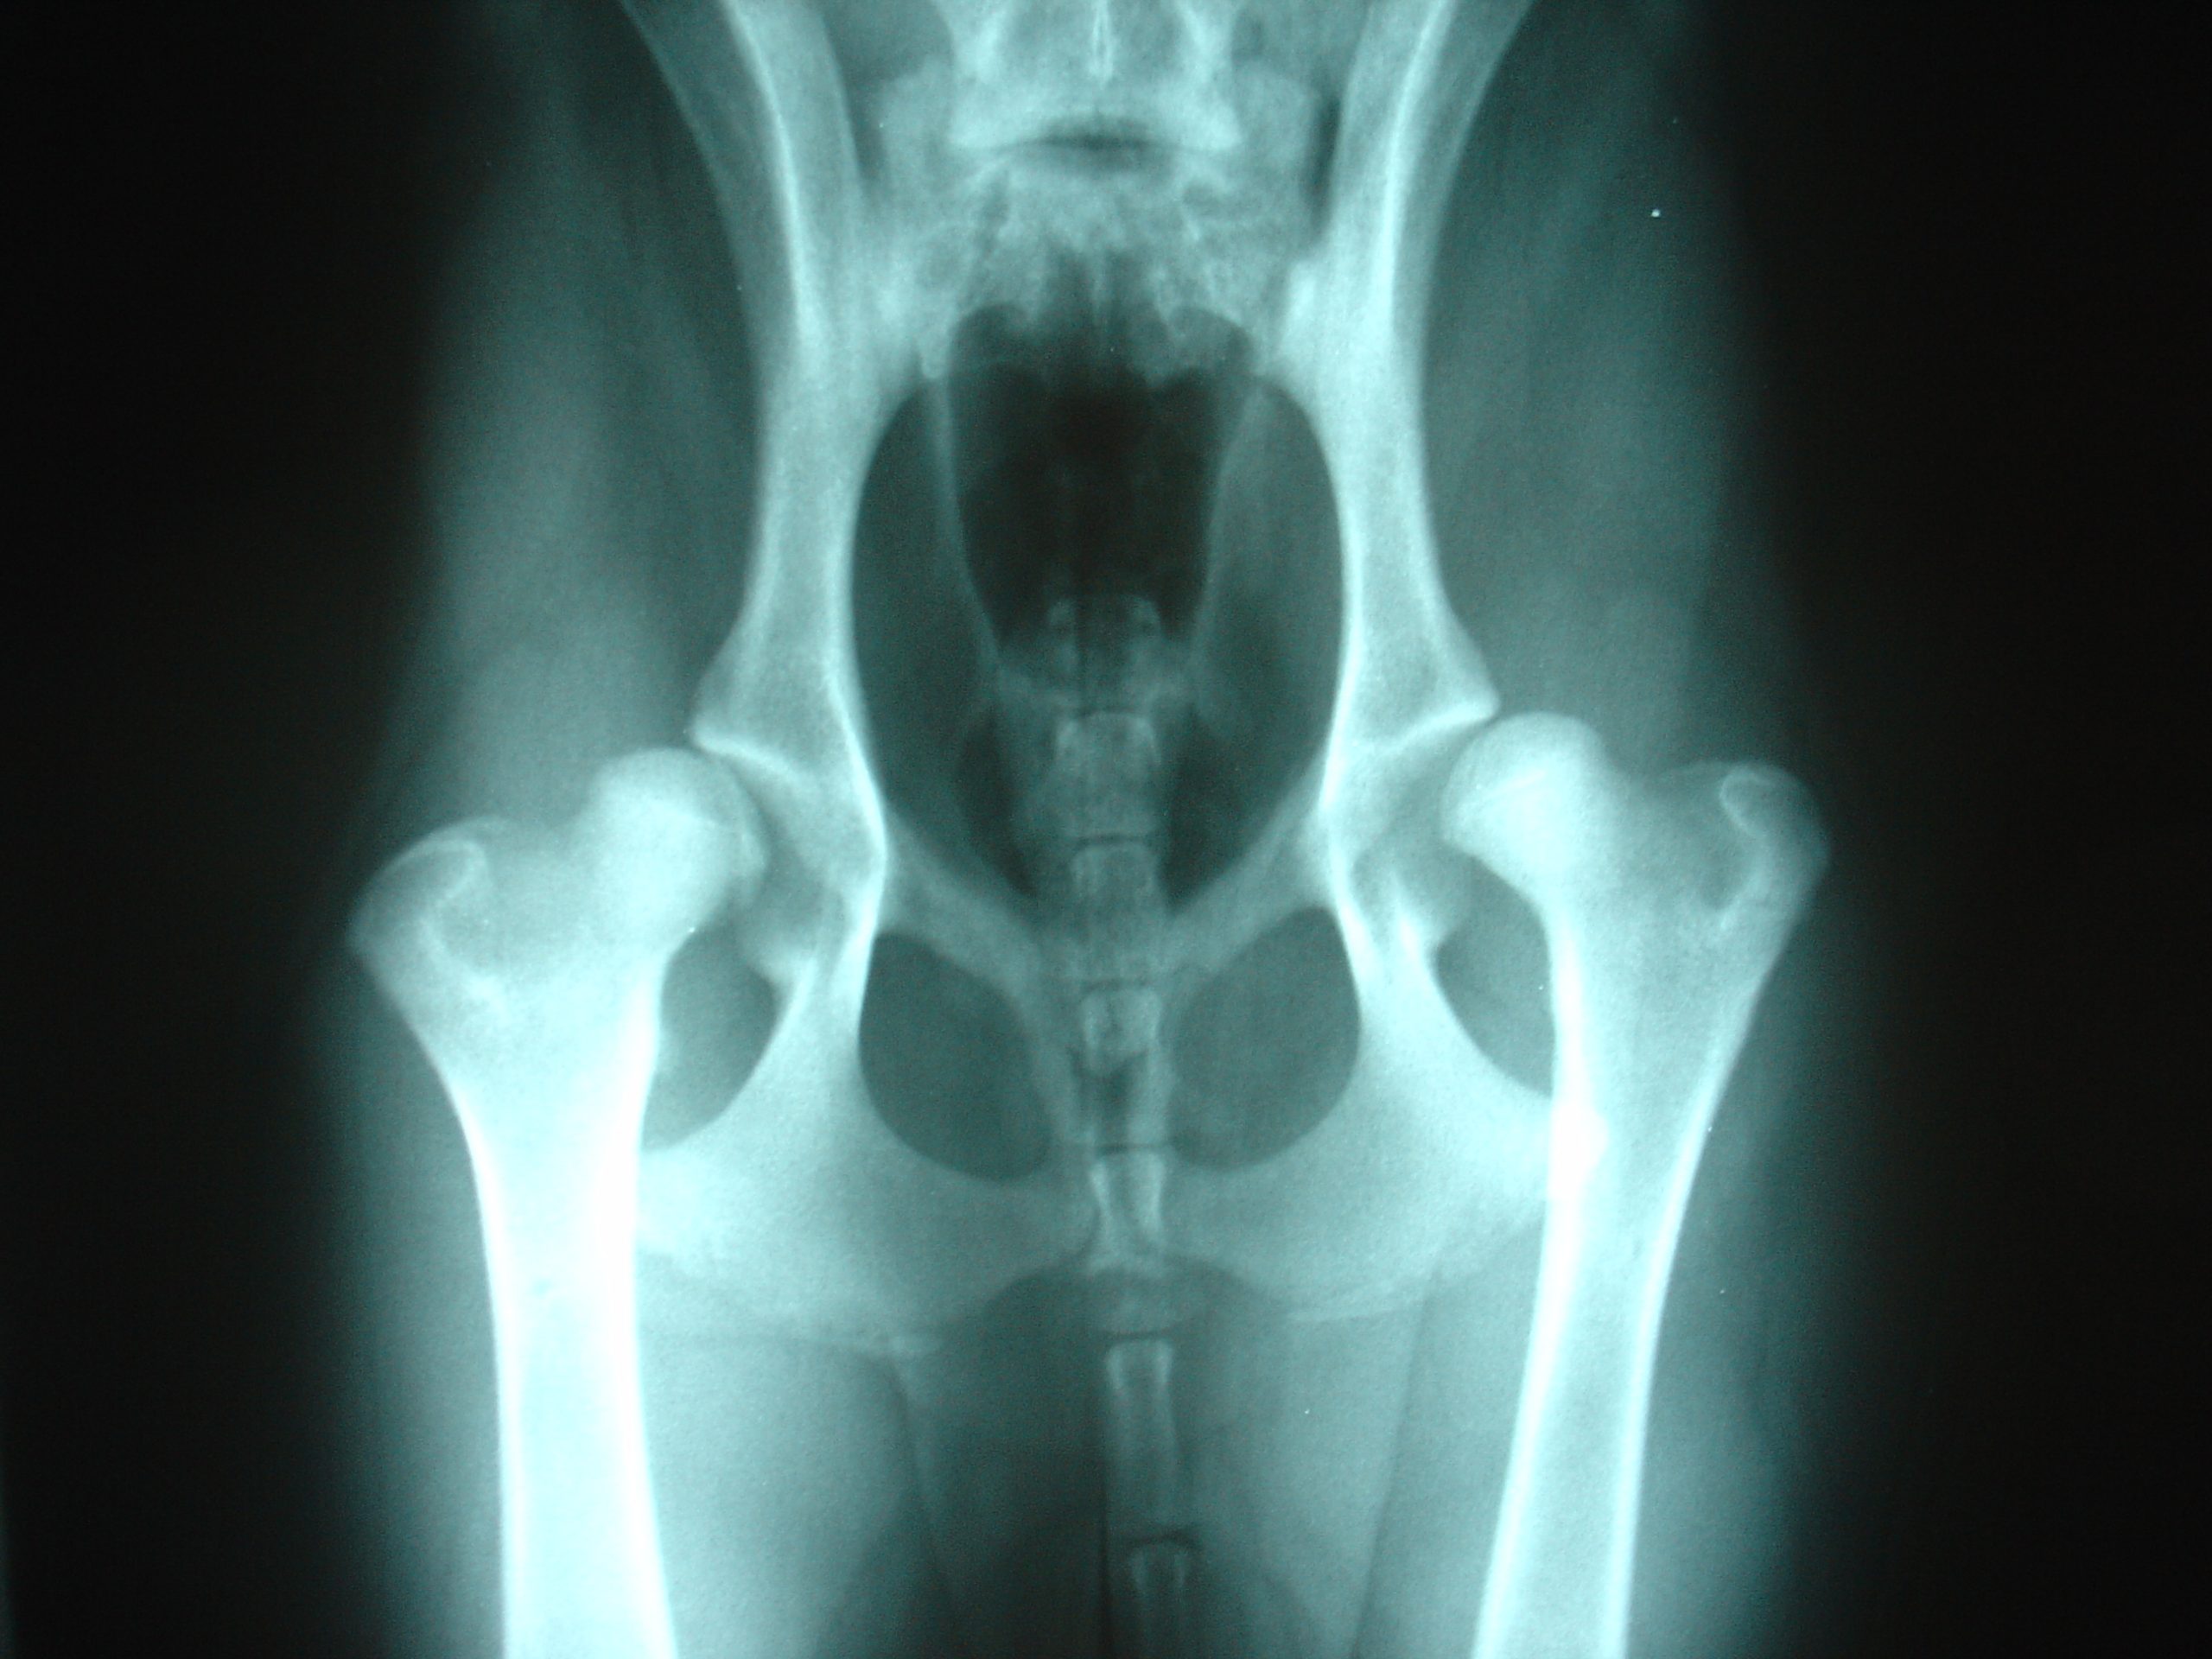

Η νόσος Legg-Calve-Perthes

Η ιδιοπαθής οστεονέκρωση της επίφυσης της μηριαίας κεφαλής 10-20% είναι αμφοτερόπλευρη. Επηρεάζεται το μυοσκελετικό σύστημα και κατά 80% σε ηλικία 4-9 ετών. Οι άνδρες επηρεάζονται περισσότερο από τις γυναίκες και η επίπτωση είναι 15/100.000.

Αρθρικές: Νόσος Legg-Calvé-Perthes (άσηπτη νέκρωση της κεφαλής του μηριαίου οστού στο ισχίο), νόσος  Kohler (του ταρσού σκαφοειδούς οστού του ποδιού), νόσος Panner (αγκώνα), και νόσος Freiberg’s (δεύτερου ή τρίτου μετατάρσιου του ποδιού και λιγότερο συχνά πρώτου ή τέταρτου).

• Ακτινογραφίες (F+P) για τον καθορισμό έκτασης βλάβης